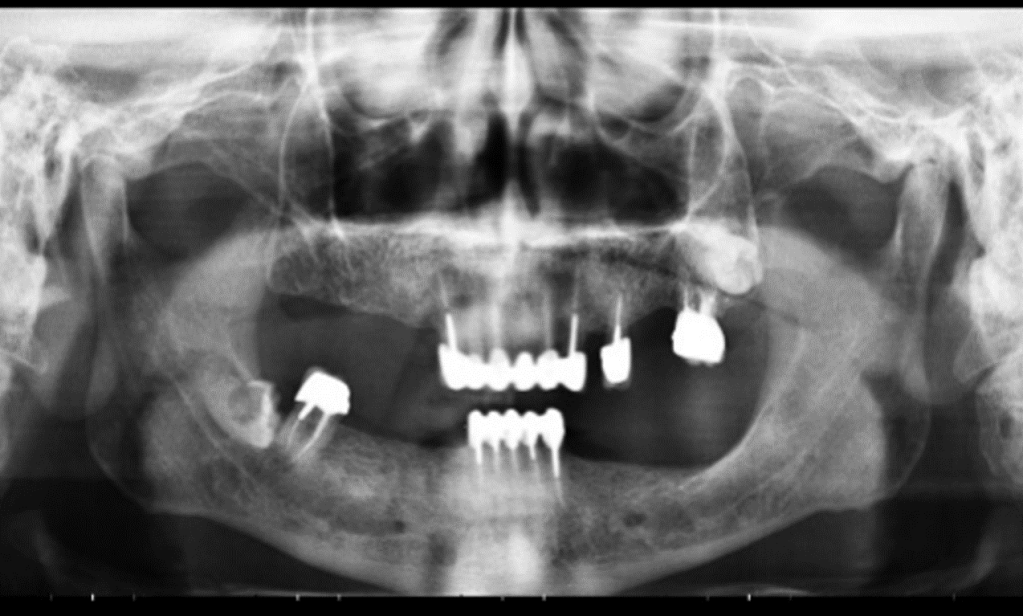

ΠΑΝΟΡΑΜΙΚΗ ΑΚΤΙΝΟΓΡΑΦΙΑ ΠΟΥ ΑΠΕΙΚΟΝΙΖΕΙ ΕΓΚΛΕΙΣΤΟ ΦΡΟΝΙΜΗΤΗ ΜΕ ΤΕΡΗΔΟΝΑ ΣΤΗΝ ΚΑΤΩ ΓΝΑΘΟ.